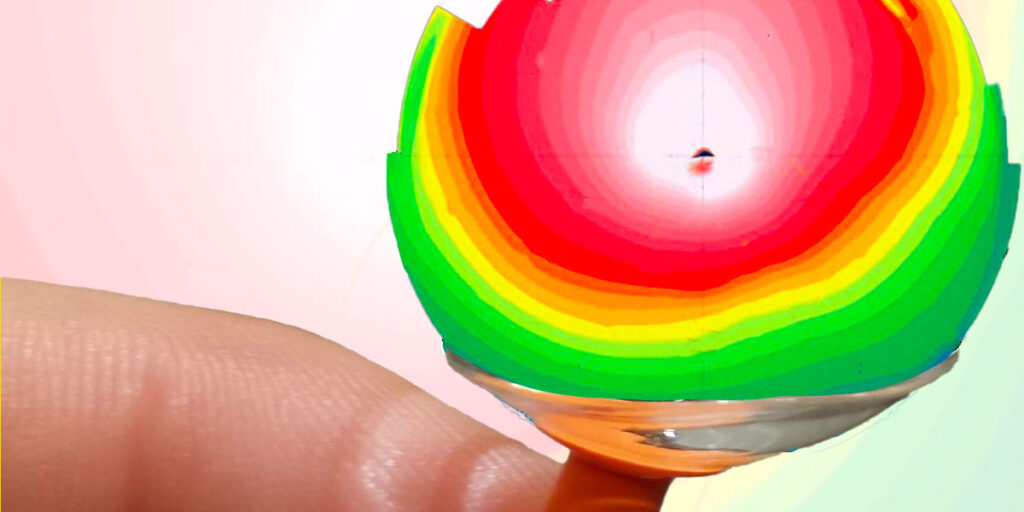

Für diejenigen, die damit nicht vertraut sind: Sklerallinsen sind eine Art von Kontaktlinsen, die die Hornhaut überbrücken und sich nur auf dem weißen Teil des Auges (der Sklera) abstützen. Die Linse ist mit steriler BSS-Lösung gefüllt, die den Raum zwischen der Hornhaut und der Linse ausfüllt. Dies macht Sklerallinsen besonders vorteilhaft für Menschen mit unregelmäßiger Hornhaut, wie z. B. unsere Patientin mit Keratokonus. Die vielen kleinen Unregelmäßigkeiten auf der Hornhautoberfläche, die zu visuellen Störungen und Aberrationen höherer Ordnung führen, werden durch die Flüssigkeit geebnet. Als Nebeneffekt kann dies auch stark trockene Augen verbessern. Am ELZA Institut haben wir unseren leitenden Optometristen, Léonard Kollros, ein sehr erfahrener, fachkundiger Skleralinsenanpasser, und der Fall, über den wir hier berichten, ist einer von ihm.